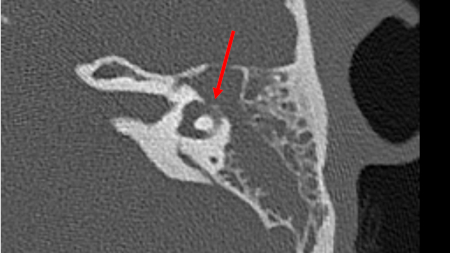

Direct erosion into the labyrinth or internal auditory canal by cholesteatoma (a collection of epidermal and connective tissues within the middle ear) increases the risk of developing labyrinthitis.[30]

[Figure caption and citation for the preceding image starts]: An axial CT (without contrast) of the temporal bone of the left ear demonstrating direct erosion into the horizontal semicircular canal by cholesteatomaFrom the personal collection of Dr Tiffany Hwa; used with permission [Citation ends].